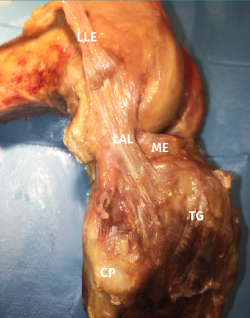

La inserción tibial ofrece menos debate, localizándose en la mayoría de las ocasiones en la mitad entre una línea que une la cabeza del peroné con el tubérculo de Gerdy(20,21)(Figura 1).

Figura 1. Imagen anatómica de la capa más profunda de la cara anterolateral de la rodilla. CP: cabeza del peroné; LAL: ligamento anterolateral; LLE: ligamento lateral externo desinsertado distalmente y reflexionado proximalmente sobre su inserción epicondílea; ME: menisco externo; TG: tubérculo de Gerdy. Imagen cedida por el Dr. D. García Germán.